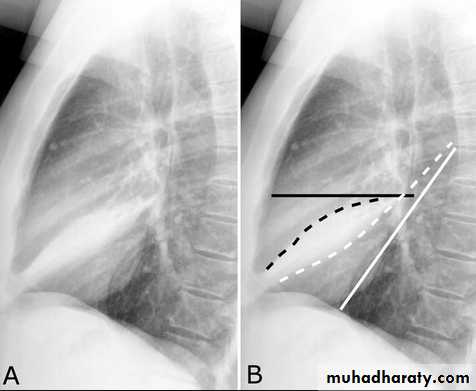

Pleural Effusion on Chest Radiographs.

Posteroanterior (A) and lateral (B) chest radiographs demonstrate the typical meniscoid appearance (arrows) in a patient with a left pleural effusion